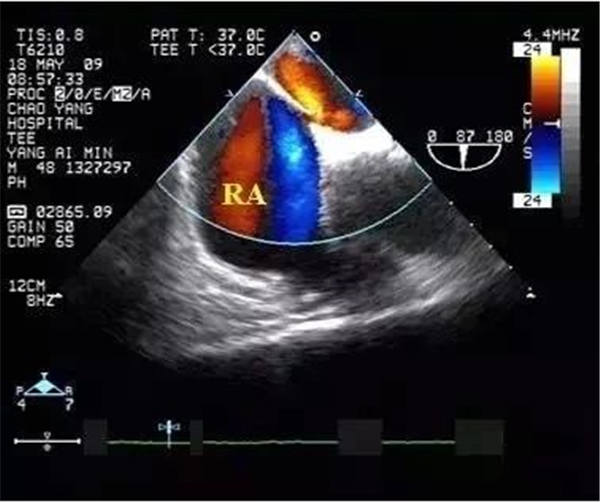

血栓

血栓是血栓性肺栓塞最典型的特征,位于右房或右室中的血栓可形態各異,而位于肺動脈內時則常表現為大塊血栓,從主干延續至一側或雙側肺動脈分支。右肺動脈主干血栓易于顯示,左肺動脈因顯示較短,血栓不易顯示。此外,需注意將血栓與右心系統腫瘤相鑒別。

右心血栓 肺動脈血栓

臨床上可通過右心聲學造影判斷卵圓孔開放與否,經食管超聲心動圖則可顯示卵圓孔分流。